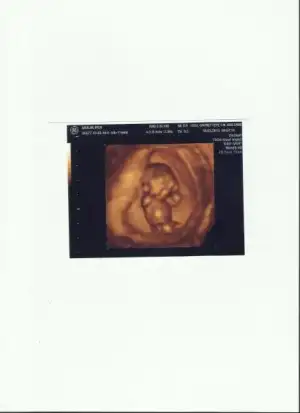

Canım ya; çok teşekkür ederim. İki fotoğraf da aynı zaten:) öbürünü yani açamadığını bir türlü düz yerleştiremedim, onun için tekrar pc'den koydum:) hadi bakalım kafam iyice karıştıaslında 10 haftalık ultrasonlarda daha net gözüküyor ve senden öğrendiğim kadarıyla paralel duruyordu da nereye koydum bulamıyorum. Ay harikasın valla:) iyi ki açmışsın bu topiği

slm cnm bende gördüm ultroson görüntüsünü oğlumunkiyle karsılastırdım banad kız gibi geldi....oğlumunki böyle değil 3 aylıkken olana baktım insallah sağlıklı sıhatlı kızın olur bende çok istiyorum oğlum 2,5 yasında sen bi yöntem bişey denedinmi hiç bide ne tarafta hissediyosun kasığının sağ taraf erkek solm kız diyolar çok kişidede tutuyo basta ben oğluma sağdan yumurtladım